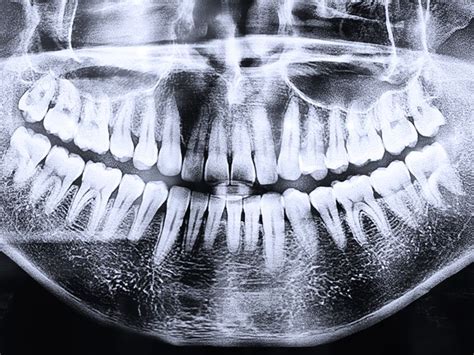

La radiografía panorámica dental, también conocida como ortopantomografía, es una herramienta fundamental en odontología que proporciona una vista completa de las estructuras dentales y maxilofaciales. Esta técnica radiológica permite obtener una imagen general de la boca a nivel panorámico, mostrando los maxilares, la mandíbula y los dientes en una sola película.

Ejemplo de radiografía panorámica dental.

Esta radiografía se realiza con un aparato llamado ortopantomografía que emplea rayos X para obtener una imagen detallada de las estructuras dentales y la anatomía oral. La radiografía panorámica es una técnica radiológica que muestra las estructuras óseas (los maxilares, la articulación de la mandíbula y los dientes) del rostro del paciente en una sola imagen general. Para ello, se vale de una máquina de rayos X especial, que rota alrededor de la cabeza del paciente.

Una de las principales ventajas de la radiografía panorámica dental es que proporciona una imagen completa de las estructuras anatómicas de la cavidad bucal y sus alrededores. Esta vista general facilita a los profesionales de la odontología evaluar y diagnosticar diversas afecciones con mayor precisión. En una radiografía panorámica se pueden ver todas las piezas dentales, incluyendo aquellas que aún no han erupcionado completamente.

Las radiografías panorámicas proporcionan una vista completa de los dientes, las encías, los huesos y los tejidos blandos de la boca. Permiten al dentista obtener una imagen precisa de las piezas dentales y los huesos de la mandíbula. Una radiografía panorámica puede realizarse en unos pocos minutos y no requiere la toma de múltiples imágenes para obtener una visión completa de la boca y los dientes. Se trata de equipos seguros y no invasivos.